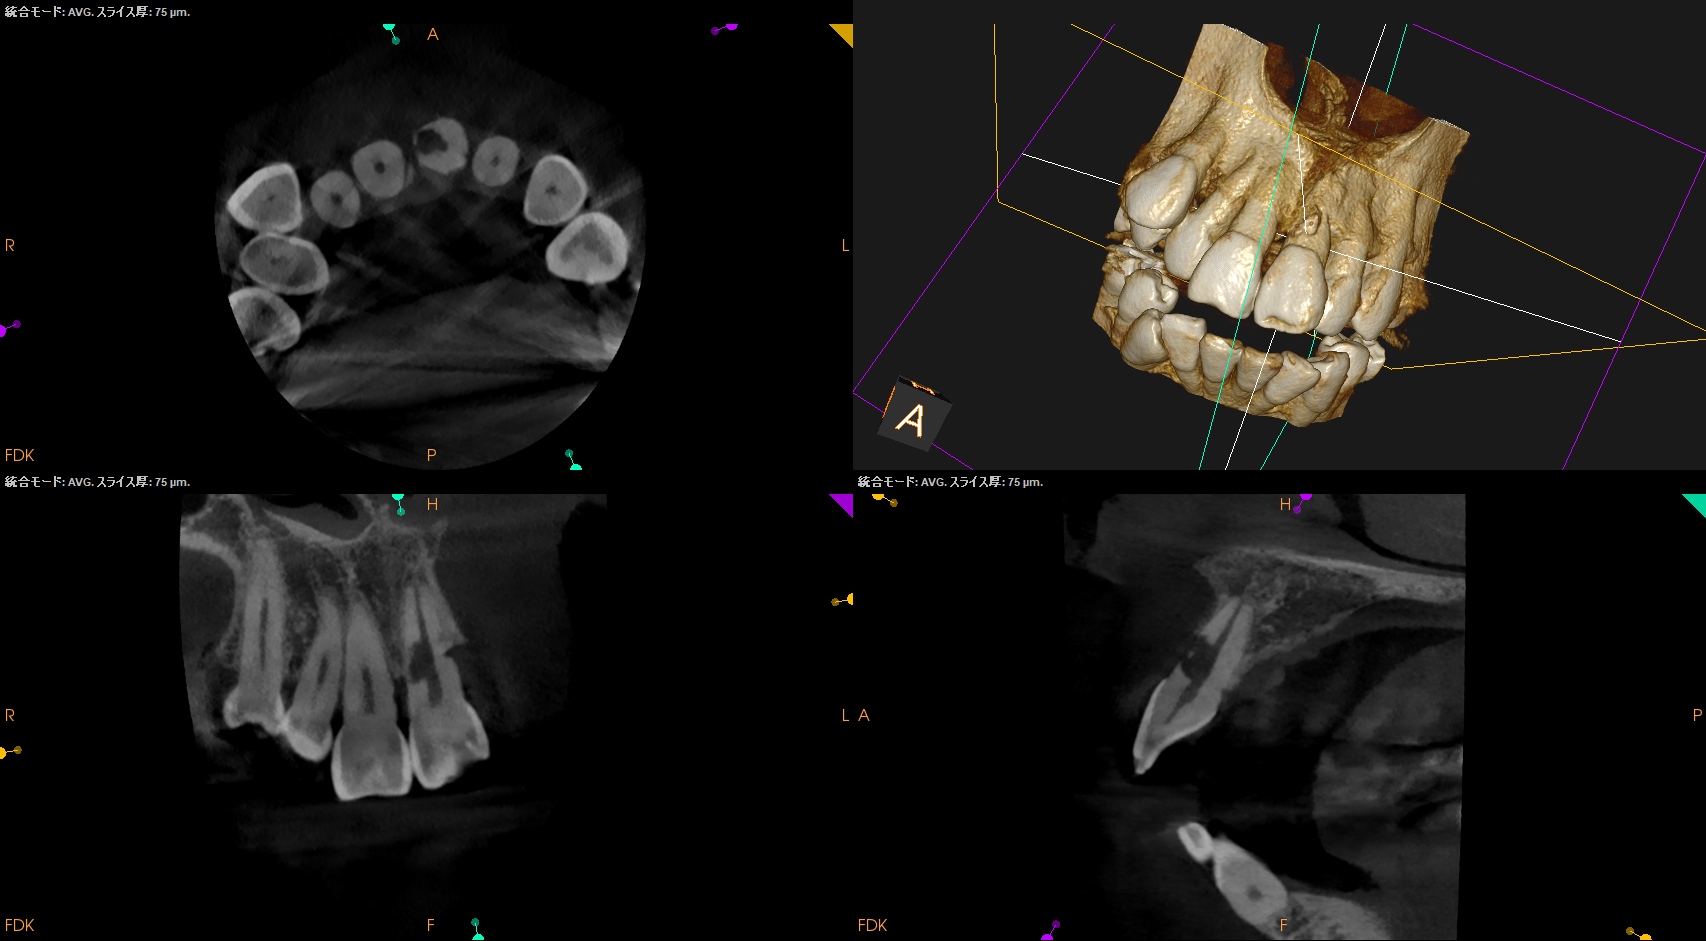

#9の頬側に大きな穴がある。が、根尖病変はない。

患者さん曰く、かつて脱落した歯を戻した(再植した)という。

根完成永久歯の再植後に、歯髄のRevascularizationは起きないことから本来は根管治療が必要だが、それがなされていないことからこの病態が発生したのかもあしれない。

また、CBCTによればそのRIL(Radiographic Instrumentation Length)は23.4mmであるということがわかる。

そこから1mm引いた22.4mm程度が作業長だろう。

このことからもCBCTがなくては治療計画も立てられないということわかるだろう。

外部吸収のRepairを行うときに根管までも封鎖してしまう可能性があるのでそこをどう処理するか?が重要だが、このCBCTの絵からはラバーダム防湿しての根管治療はほぼ無理である。